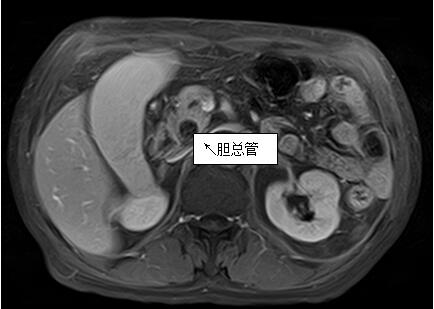

69歲王姓患者,因“發(fā)現(xiàn)無痛性黃疸1月”入院,根據(jù)患者病史,患者診斷傾向于壺腹部腫瘤所致梗阻性黃疸。予以完善腹部CT及上腹部MRI加MRCP均顯示肝內(nèi)外膽管擴(kuò)張,未發(fā)現(xiàn)明顯膽管,胰腺及十二指腸乳頭部腫瘤,且患者CA199正常。以前醫(yī)院未引進(jìn)超聲內(nèi)鏡,這類患者到此就遇到診斷瓶頸。此患者經(jīng)過消化內(nèi)科張丹霞副主任醫(yī)師完善超聲內(nèi)鏡檢查后,可以清楚顯示膽總管下段壁內(nèi)軟組織占位。患者通過超聲內(nèi)鏡檢查診斷明確,轉(zhuǎn)至肝膽外科行手術(shù)治療。

上腹部MRI圖片